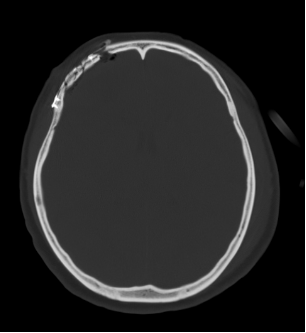

图5(妻子术前CT显示颅骨凹陷粉碎性骨折)

图6 (妻子术后CT显示颅骨骨折整复术后)